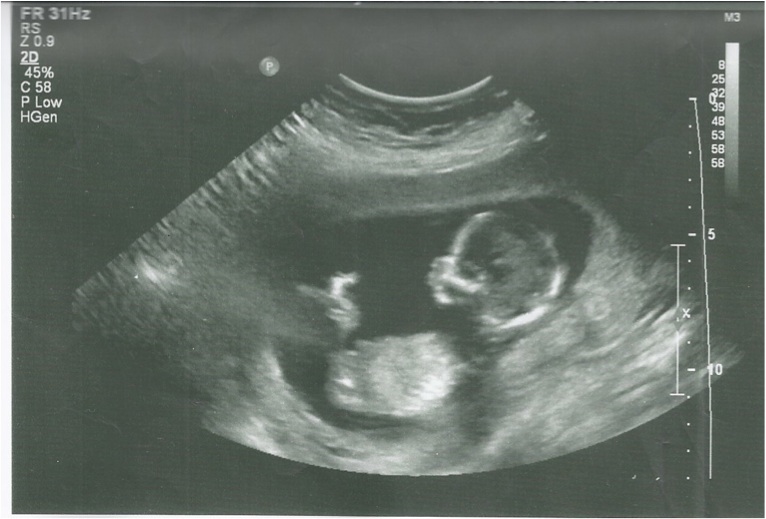

No gender clues that I can see

Not good gender pics. BUT...in the third one, there appears to be something questionable between the legs. I would guess boy. But it's a complete amateur guess.

Definitely see boy parts in your third pic. Did the tech tell you? Congrats

I agree - third piccy looks like a boy. Congrats! Which are you hoping for? x